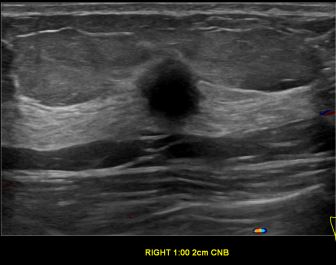

상기환자는 외부검사 이상소견으로 내원하신 70대초반 여성분으로 의심스러운 우측혹 조직검사 시행해 유방암으로 진단되었습니다